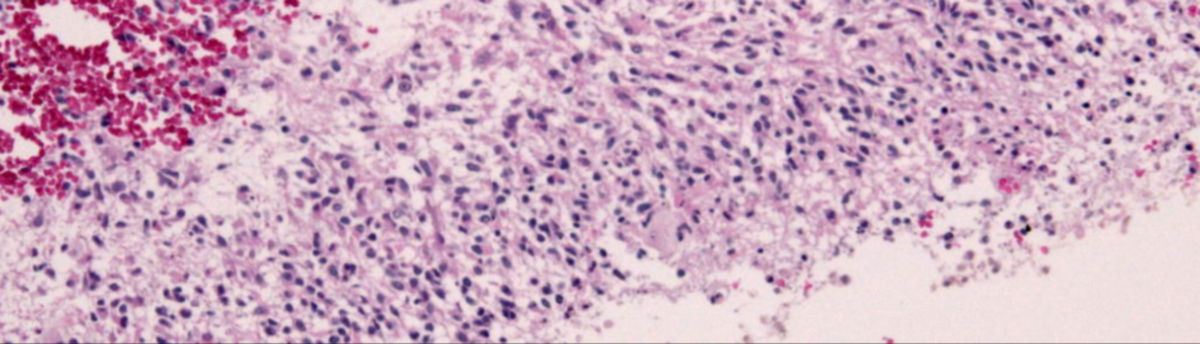

Bei dieser Form finden sich große Epitheloidzellen mit reichlich eosinophilem Zytoplasma, sie erinnern an Melanomzellen. Manchmal sind auch Rhabdoidzellen dabei. In etwa 50 % lassen sich BRAF V600E Mutationen nachweisen.